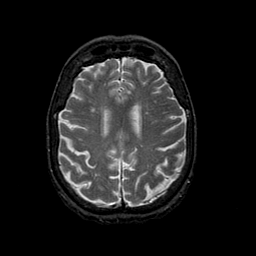

Normal aging, overlay -- Slice #36

[Home][Help][Clinical] Slice 36